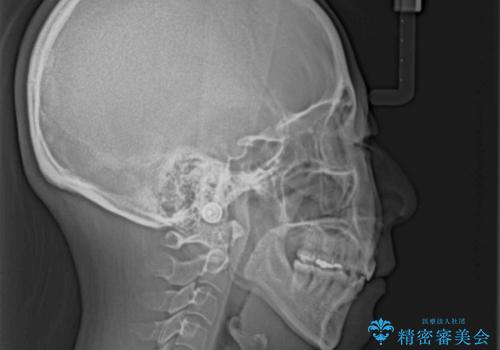

- 出っ歯と口の閉じにくさ、デコボコを気にして来院された患者様です。

口元の突出感を改善するため、上下左右第一小臼歯4本の抜歯を行い、ワイヤー装置による矯正治療を行うこととしました。

上下前歯の距離が大きかったため、上下の歯が接触するまでに時間がかかりました。

それでも目安である2年半で終えることができ、患者様には大変満足していただけました。